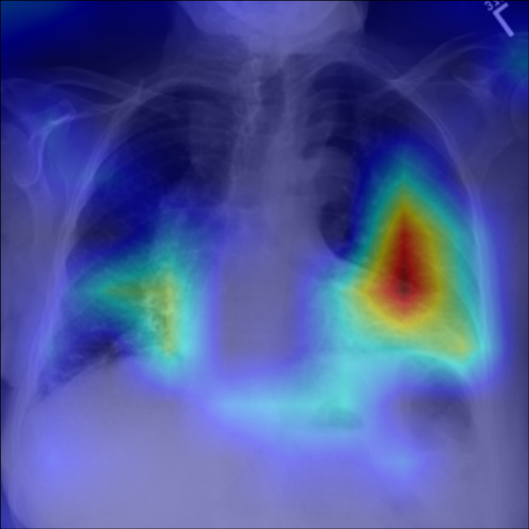

Refer to caption

Figure 5: Visualization of attention map in PLAN on MS-CXR. The red boxes indicate the corresponding ground truth of grounding. Highlighted pixels represent higher activation weights correlating specific words with regions in the image.

IV-B1 Phrase Grounding

Phrase grounding associates textual phrases (e.g., disease descriptions or anatomical terms) with corresponding regions in medical images, offering precise diagnostic insights and enhancing model interpretability. Table II presents the phrase grounding results on the MS-CXR dataset. Using the Contrast-to-Noise Ratio (CNR) [27] as the evaluation metric, PLAN achieved the highest CNR across eight disease categories, outperforming MGCA and PRIOR. Heatmaps generated with Grad-CAM (Figure 4) further illustrate PLAN’s ability to accurately localize lesion sites and align disease-related phrases with image regions. Additional comparisons with baseline methods can be found in Figure 5. These findings highlight PLAN’s superior precision and interpretability in phrase grounding tasks.